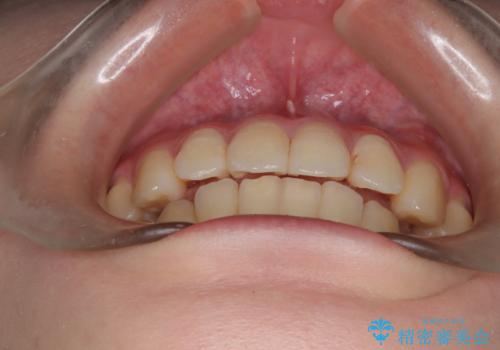

- 上下の前歯に捻れ(捻転)とガタつき(叢生)が見られます。

上の2番目の前歯の捻れに関しては、元々歯の大きさが小さい歯であるため、マウスピースにて力がかかりにくく、捻転の改善が一般的に難しくなりがちです。

下の犬歯に関しても捻れと傾き、ガタつきが大きく、歯根の長さも相まって移動の難易度が高くなりがちです。

インビザラインのそうした特色を踏まえた上で、それらをリカバーできるように治療方式の調整を十分に行い、治療を進めました。